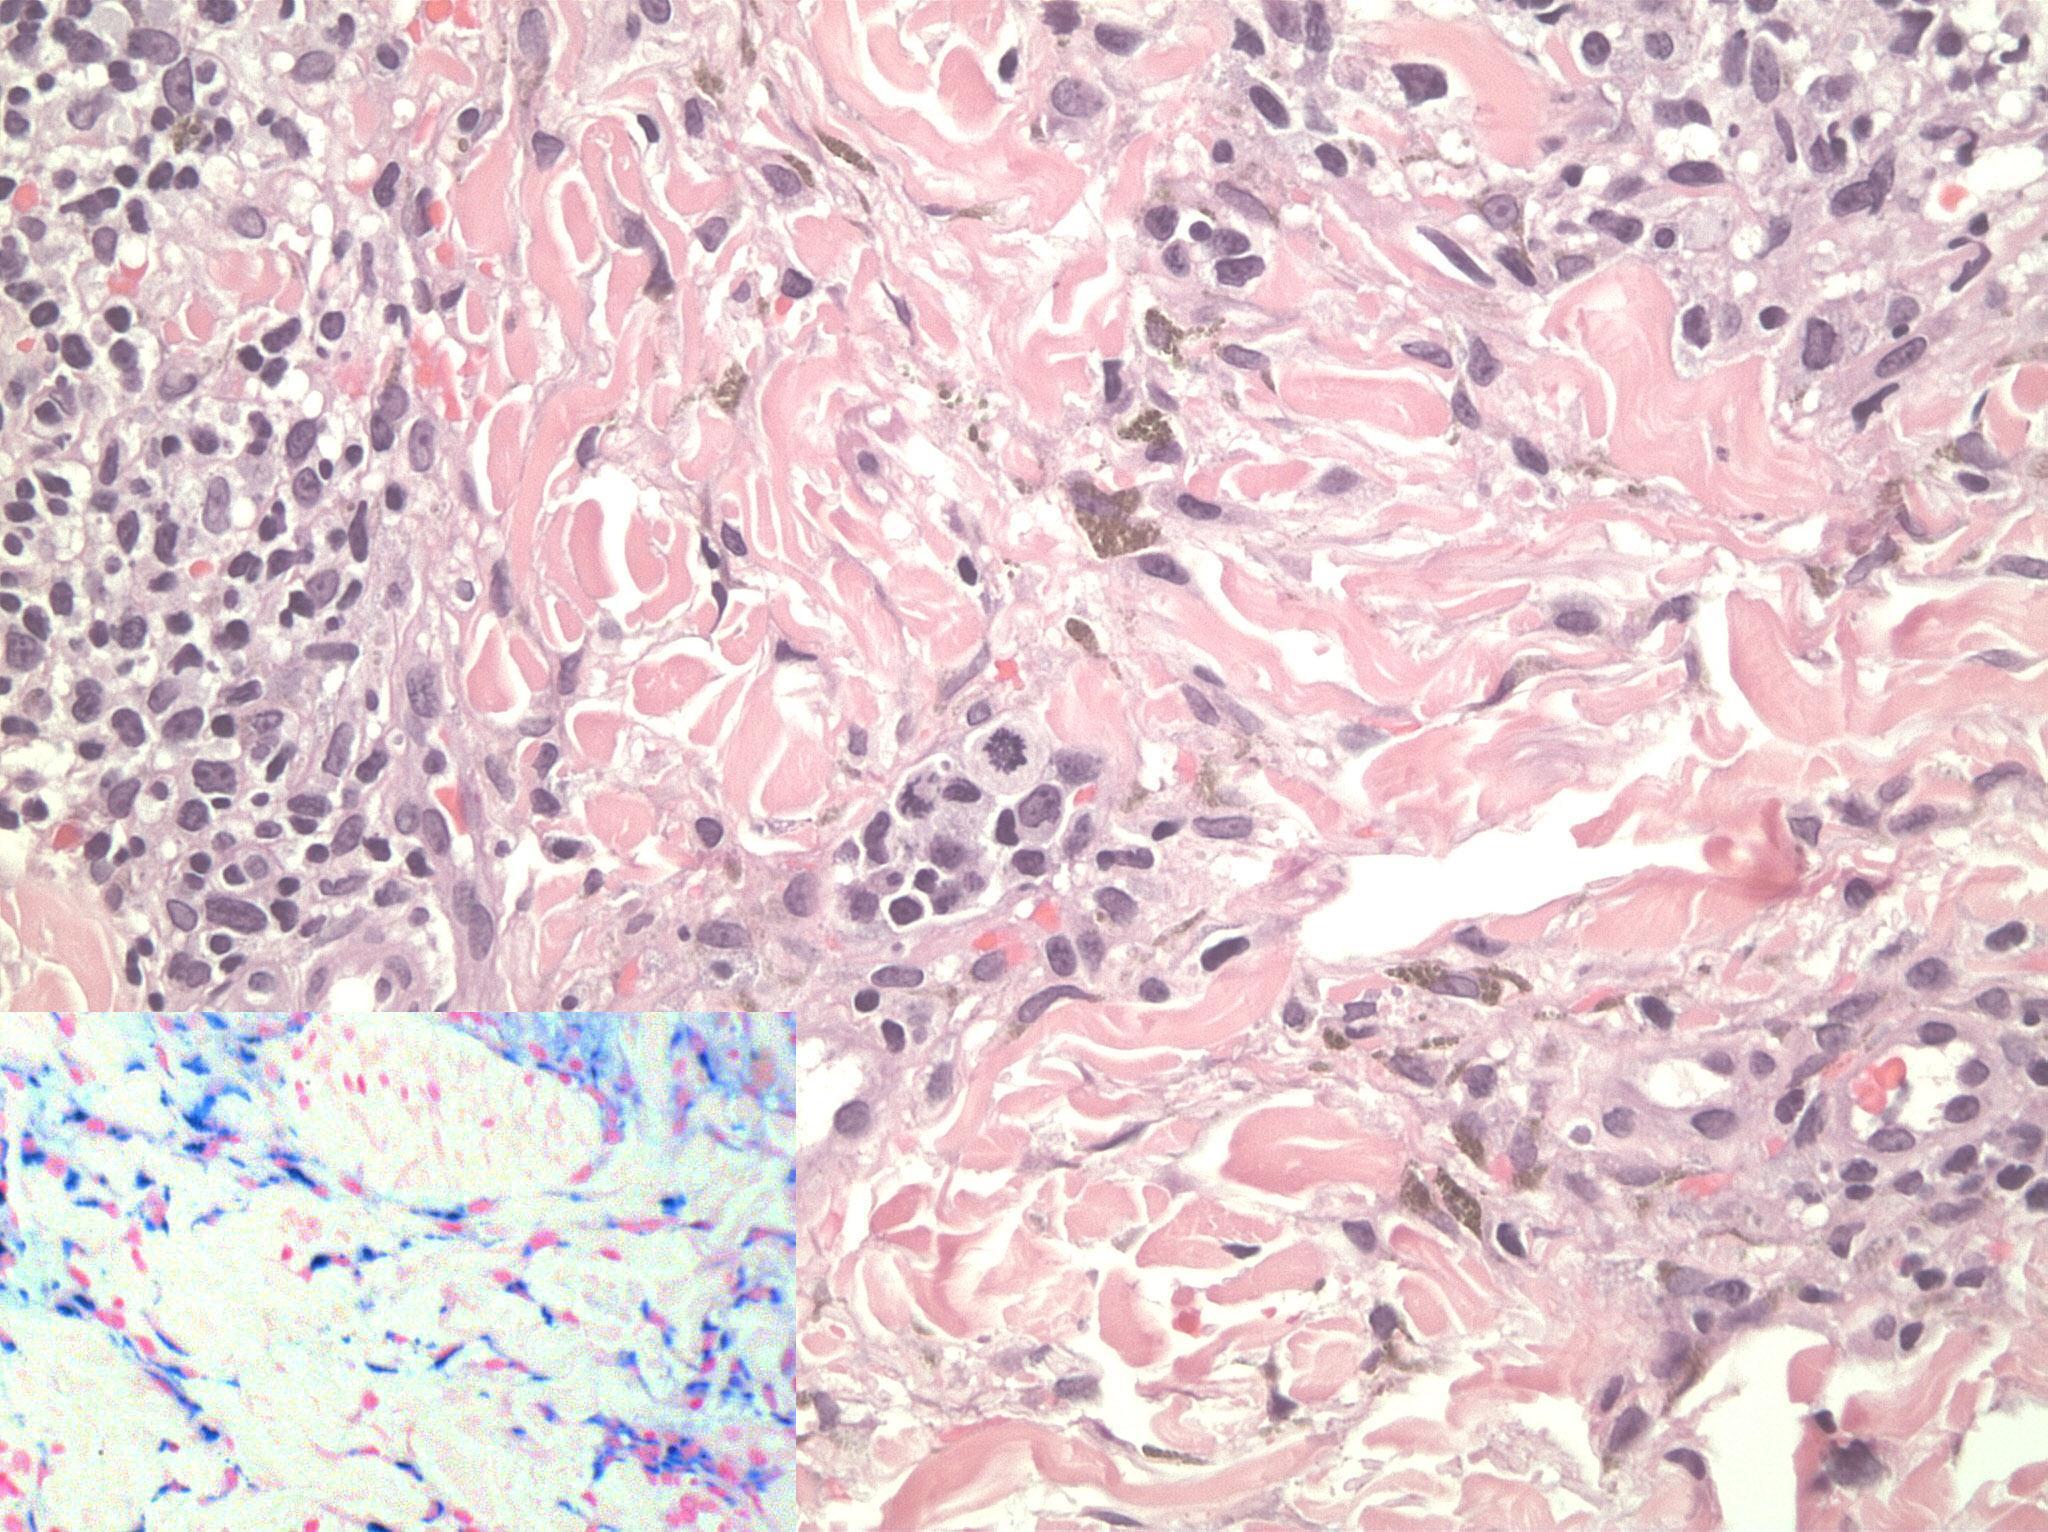

A 30-year-old man presented with a 4-month history of increased facial pigmentation. The patient reported that this had occurred 3 months after being started on oral isotretinoin (40 mg daily) for the treatment of acne vulgaris. He was otherwise healthy and not on any other drug therapy. In addition, he denied using any facial creams at the time when the problem had started. Moreover, he denied family history of similar condition or photodermatosis. On examination, the patient had well-demarcated hyperpigmented patches and plaques on an erythematous purpuric background (Figure 1). The changes were mainly observed on sun exposed surfaces. A punch biopsy was done and revealed dermal lymphohistiocytic infiltrates with scattered eosinophils, extravasated erythrocytes, and prominent hemosiderin deposition highlighted by iron stain (Figure 2). Fontana-Masson stain revealed no increase in melanin in the dermis or epidermis and immunohistochemical staining using MART-1 revealed normal melanocyte number at the basal cell layer of the epidermis.

Figure 2.Histology revealed dermal lymphocytic infiltrates with scattered eosinophils, extravasated erythrocytes, and hemosiderin deposition (original magnification, 20). Inset: Perl’s stain highlights hemosidrin depostion (original magnification, 40).

Histology revealed dermal lymphocytic infiltrates with scattered eosinophils, extravasated erythrocytes, and hemosiderin deposition (original magnification, 20). Inset: Perl’s stain highlights hemosidrin depostion (original magnification, 40).